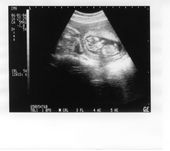

Tulia 12 week ultrasound

5.4 cm Long

12 Weeks 1 Day (+/-6Days) Old

This is when we told everyone. The baby was doing flips and waving when we did the ultrasound (no kidding!) We got to see a better photo but the one we ended up with wasn't the best. Still you can see the hands and feet. The head is on the left side.